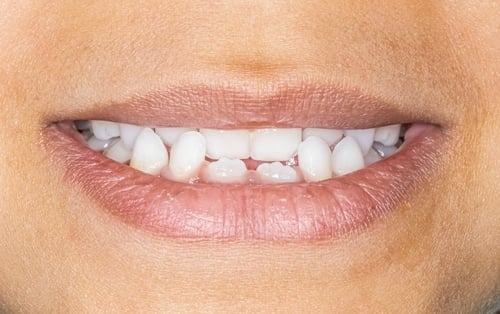

其中很常見的一種情況,是鼻上顎複合體(上顎骨)發育不足。當上顎不夠寬,牙齒就像被安排在過小的空間裡,自然容易出現擁擠、凌亂、暴牙、虎牙長不出來等狀況。更重要的是,上顎骨同時也是鼻腔底部的重要結構。如果上顎太窄,鼻腔也可能跟著變窄,使孩子鼻呼吸阻力增加,久而久之形成口呼吸、睡覺張口、打鼾等問題。

- 暴牙越來越明顯

- 虎牙沒有足夠位置萌發

- 暴牙

- 虎牙或萌發空間不足變埋伏齒

- 笑容過窄(頰側黑走廊明顯)